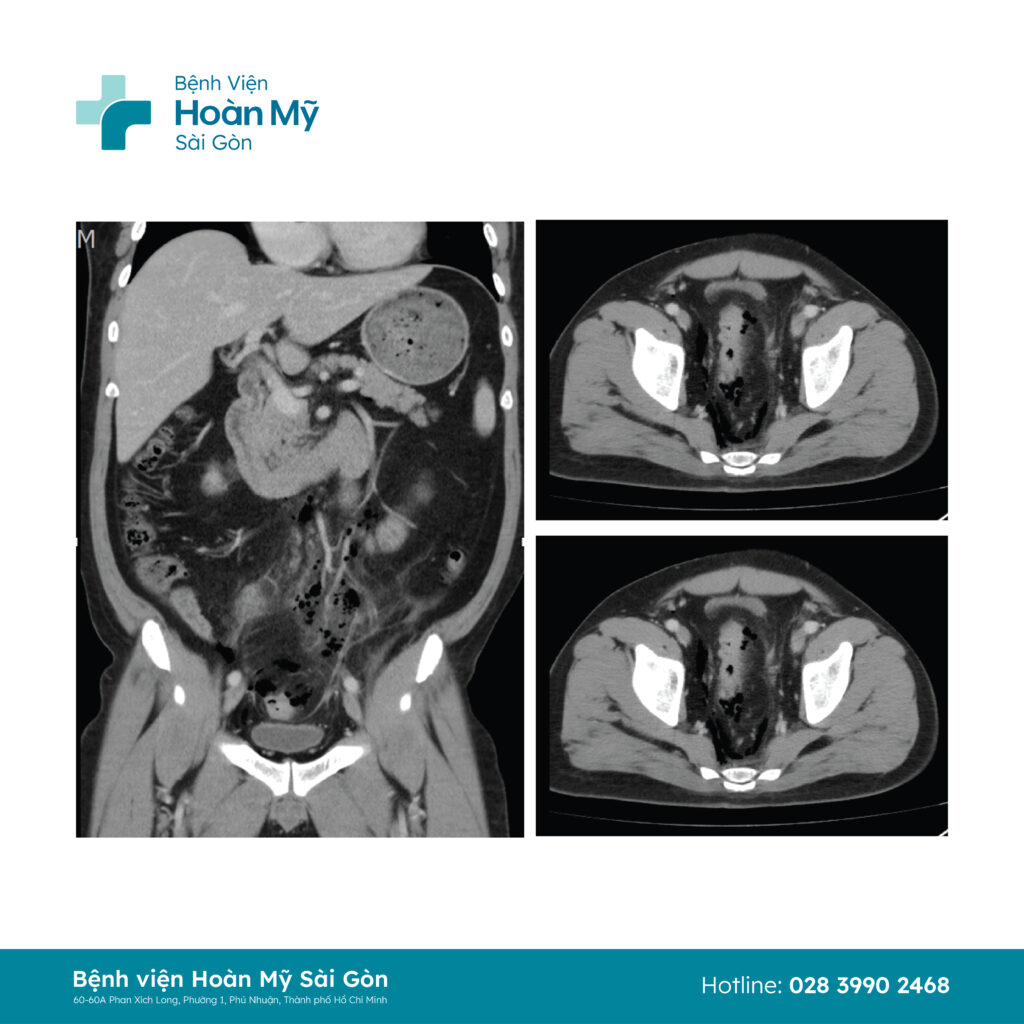

Tại bệnh viện, anh T. được thăm khám lâm sàng, nghi ngờ tình trạng thủng ruột và được chỉ định chụp cắt lớp vi tính bụng chậu, đồng thời thực hiện các xét nghiệm máu.

Kết quả cho thấy anh T. bị đa túi thừa đại tràng chậu hông, trực tràng kèm thâm nhiễm mô mỡ, dịch xung quanh, đặc biệt là khí tự do kéo dài dọc mạc treo đại trực tràng, lan xa đến hạ vị. Anh được chẩn đoán viêm túi thừa đại tràng chậu hông giai đoạn WSES 2B (túi thừa viêm thủng, khí tự do di chuyển xa trong ổ bụng), ngay lập tức anh T. được chỉ định phẫu thuật cấp cứu, nội soi ổ bụng, rửa bụng, cắt đoạn ruột chứa túi thừa viêm thủng và nối ruột một thì.

Ảnh chụp cắt lớp vi tính cho thấy túi thừa đại tràng thâm nhiễm mỡ xung quanh